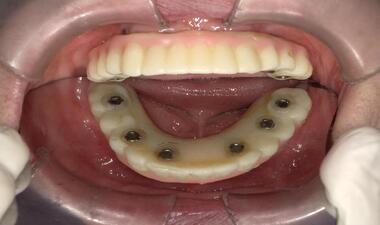

術中

下顎缺牙,植入六顆植體